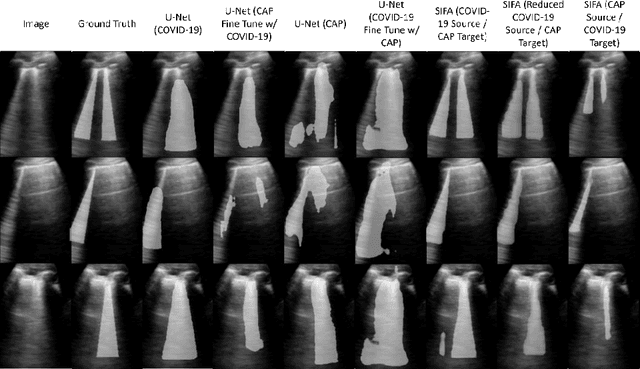

Lung ultrasound imaging has been shown effective in detecting typical patterns for interstitial pneumonia, as a point-of-care tool for both patients with COVID-19 and other community-acquired pneumonia (CAP). In this work, we focus on the hyperechoic B-line segmentation task. Using deep neural networks, we automatically outline the regions that are indicative of pathology-sensitive artifacts and their associated sonographic patterns. With a real-world data-scarce scenario, we investigate approaches to utilize both COVID-19 and CAP lung ultrasound data to train the networks; comparing fine-tuning and unsupervised domain adaptation. Segmenting either type of lung condition at inference may support a range of clinical applications during evolving epidemic stages, but also demonstrates value in resource-constrained clinical scenarios. Adapting real clinical data acquired from COVID-19 patients to those from CAP patients significantly improved Dice scores from 0.60 to 0.87 (p < 0.001) and from 0.43 to 0.71 (p < 0.001), on independent COVID-19 and CAP test cases, respectively. It is of practical value that the improvement was demonstrated with only a small amount of data in both training and adaptation data sets, a common constraint for deploying machine learning models in clinical practice. Interestingly, we also report that the inverse adaptation, from labelled CAP data to unlabeled COVID-19 data, did not demonstrate an improvement when tested on either condition. Furthermore, we offer a possible explanation that correlates the segmentation performance to label consistency and data domain diversity in this point-of-care lung ultrasound application.